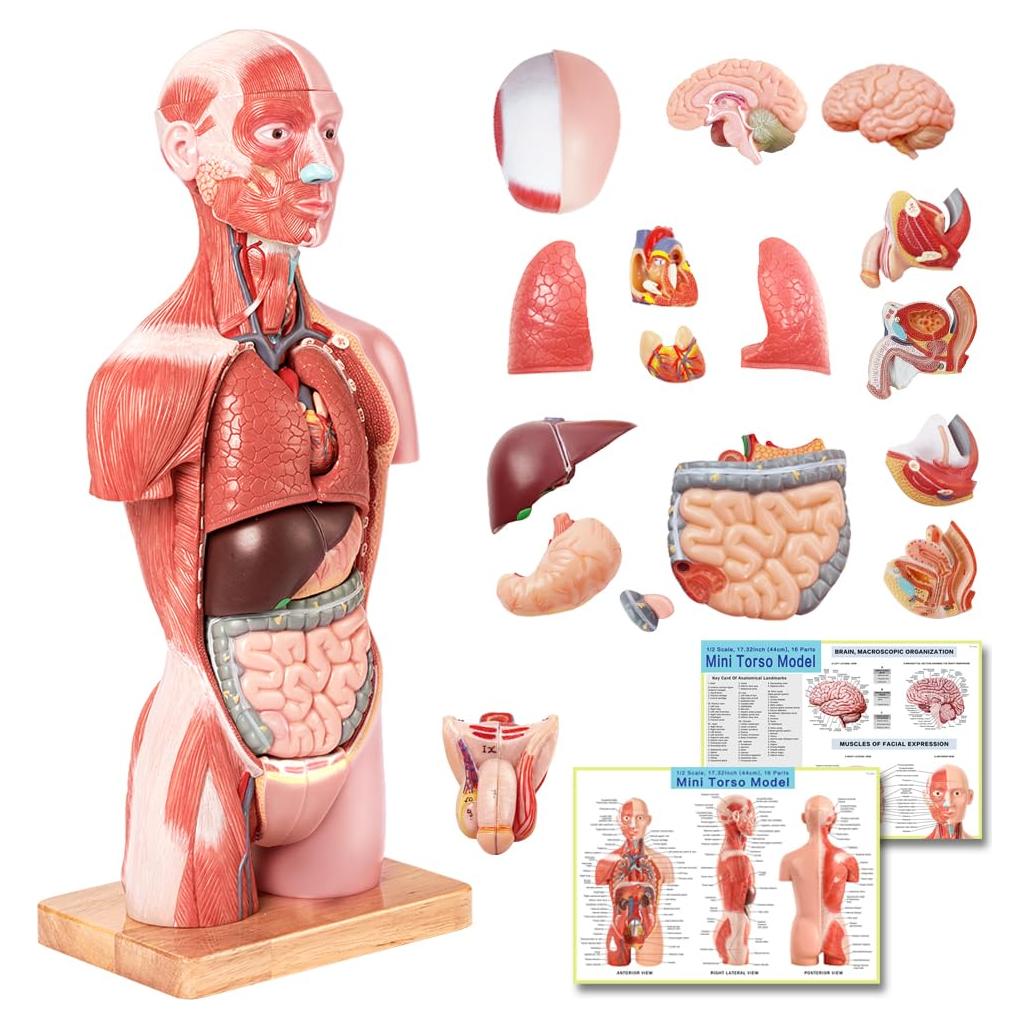

Modelos Anatómicos de Órganos marca Evotech (20 productos)

Modelos Anatómicos 3D EVOTECH SCIENTIFIC - Cuerpo, Corazón y Esqueleto